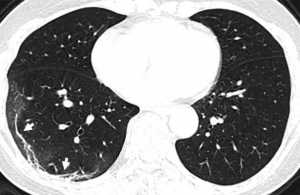

Οι σαρώσεις του, που δόθηκαν στη δημοσιότητα από την Ακτινολογική Εταιρεία της Βόρειας Αμερικής, δείχνουν λευκά στίγματα στις κάτω γωνίες των πνευμόνων του, πράγμα που υποδηλώνει τη μερική πλήρωση των αεραγωγών.

Και όταν συγκρίνουμε την εικόνα Α με την εικόνα F, δείχνει πώς το υγρό στους χώρους των πνευμόνων του ανθρώπου έγινε πιο έντονο με την πάροδο του χρόνου.

Άλλες σαρώσεις μιας 54χρονης γυναίκας που προσβλήθηκε από τον κορονοϊό μετά από ταξίδι στο Γουχάν, δείχνουν επίσης την ίδια μερική πλήρωση των αεραγωγών.